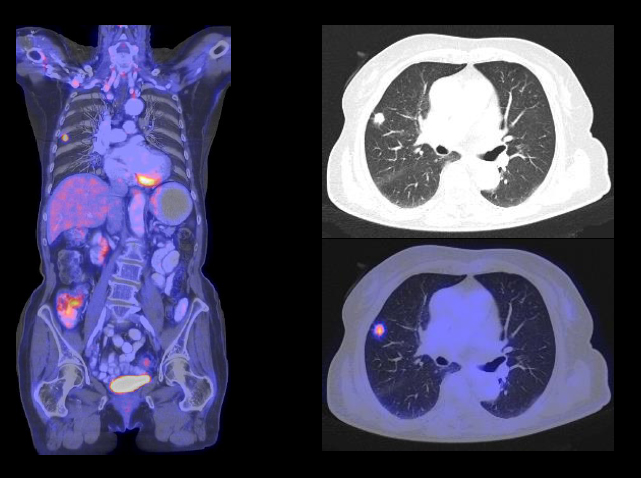

PET(Positron Emission Tomography)検査とは、「陽電子放射断層撮影装置」を用いた検査のことで、腫瘍組織や心臓・脳などの働きを断層画像としてとらえる新しい検査方法です。ブドウ糖を多量に摂取するがん細胞の特性を利用し、細胞がどのような働きをしているかを診ることで、がんの有無や位置、進行具合などのほか、腫瘍の良性・悪性の鑑別などを行うことができます。

がんに対するPET/CT検査では主にFDGというブドウ糖に似た薬剤を用います。このFDGはブドウ糖にポジトロン核種の一つ、フッ素(18F)を結合させた物質です。

これを人体に投与するとブドウ糖の取り込みの盛んな部位、臓器にFDGが取り込まれます。FDGからはγ線が放出されますからこれをPET装置で捉えて画像化できるのです。ブドウ糖は代謝が盛んな脳や肝臓、また排泄経路である腎臓や膀胱に多く集まります。一方病気で取り込みが増える代表的なものは悪性腫瘍です。活発な細胞分裂をする悪性腫瘍、がんは正常の3-8倍のブドウ糖を取り込み、同時に多くのFDGも取り込みます。PETではこれを検出して、体のどの部分にがん細胞があるのか、注射1本で検出することが可能です。

がん細胞は、正常な細胞に比べて活動が活発なため、3〜8倍のブドウ糖を取り込むという特徴があります。

PET/CT検査は、その特徴を利用してたくさんブドウ糖を取り込んでいる細胞を探し、がんを発見します。